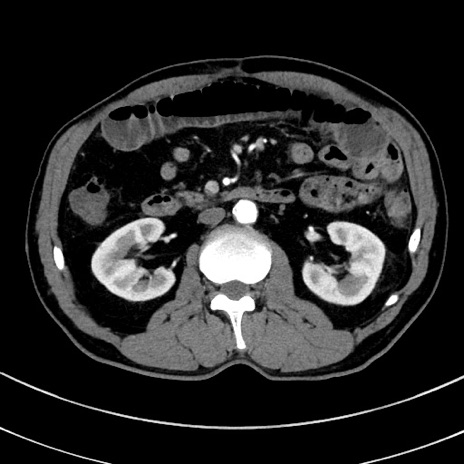

冠状断像

【症例】 60歳代男性

【主訴】 黒色吐物

【現病歴】 4日前から嘔気自覚、2日前の朝食後にも嘔気あり、自分で手で嘔吐反射起こし嘔吐したところ血が混ざっていたため受診。

【既往歴】 5年前汎発性腹膜炎を伴う急性虫垂炎で手術、高血圧、前立腺肥大症、高脂血症

【身体所見】 腹部正中に手術癩痕あり 腹部平坦・軟圧痛なし膨満感あり

【データ】WBC 8400、CRP 4.54